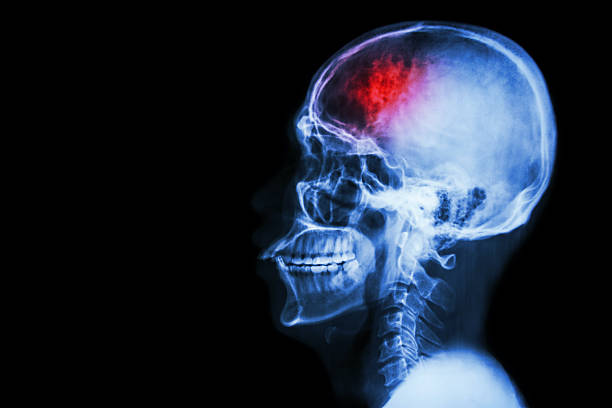

뇌출혈은 두 개 내에 출혈이 있어 생기는 모든 변화를 말하는 것으로 가장 큰 원인으로는 고혈압 증상을 지목하곤 합니다. 고혈압은 산소와 영양소가 뇌로 들어가는 통로인 혈관에서 변화를 일으키기 때문인데 뇌동맥류가 손상된 경우에도 발생할 수 있으며 잦은 흡연이나 음주 등 여러 원인으로 합병증으로 인해 발생할 수 있습니다. 특히, 뇌출혈 증상 발생시 가능한 빨리 병원으로 가야하고 약 2시간 안에 응급처치를 받아야 하는데 이는 응급처치를 받지 않으면 바로 뇌 손상으로 사망에 이를 수 있기 때문에 이번 시간에는 뇌출혈 전조증상에 대해 정리해 보겠습니다.